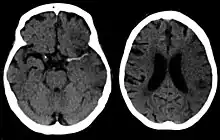

A CT showing early signs of a middle cerebral artery stroke with loss of definition of the gyri and grey white boundary

Dens media sign in a patient with middle cerebral artery infarction shown on the left. Right image after 7 hours.

Stroke is diagnosed through several techniques: a neurological examination (such as the NIHSS), CT scans (most often without contrast enhancements) or MRI scans, Doppler ultrasound, and arteriography. The diagnosis of stroke itself is clinical, with assistance from the imaging techniques. Imaging techniques also assist in determining the subtypes and cause of stroke. There is yet no commonly used blood test for the stroke diagnosis itself, though blood tests may be of help in finding out the likely cause of stroke.[63]

CT scans may not detect an ischemic stroke, especially if it is small, of recent onset, or in the brainstem or cerebellum areas. A CT scan is more to rule out certain stroke mimics and detect bleeding.[9]